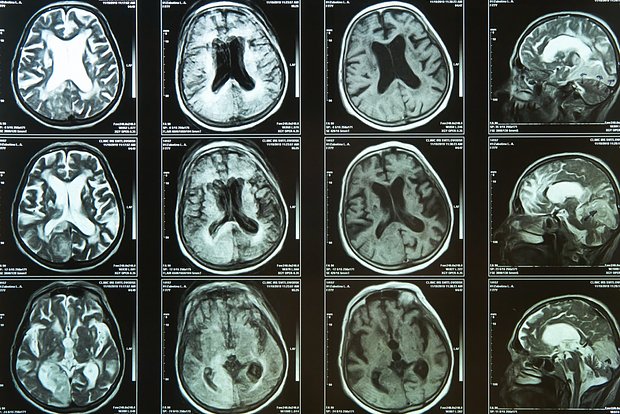

Ученые Кембриджского университета представили препарат, который может в разы сократить повреждение мозга после инсульта. В эксперименте на мышах вещество под названием кислотный малонат (aDSM), введенное в мозг при восстановлении кровотока, уменьшило объем поврежденных тканей на 60 процентов. Результаты исследования опубликованы в журнале Cardiovascular Research.

После инсульта одна из главных проблем — это не только блокировка кровотока, но и его резкое восстановление. Когда кислород снова поступает в пострадавшую ткань, в клетках запускается цепная реакция, вызывающая выброс свободных радикалов. Это может усиливать воспаление и разрушать ДНК, усугубляя исход даже при успешной тромбэктомии — стандартной процедуре удаления тромба.

Исследователи выяснили, что повреждение запускается за счет окисления вещества сукцината. Препарат aDSM блокирует этот процесс, проникая через гематоэнцефалический барьер благодаря небольшой кислотности раствора.

Авторы отмечают: чем меньше зона поврежденной ткани, тем выше шанс пациента сохранить речь, движение и когнитивные функции. Сейчас метод тестируют в рамках стартапа Camoxis Therapeutics — в перспективе он может применяться и при других состояниях, связанных с резким восстановлением кровотока, включая инфаркт и пересадку органов.